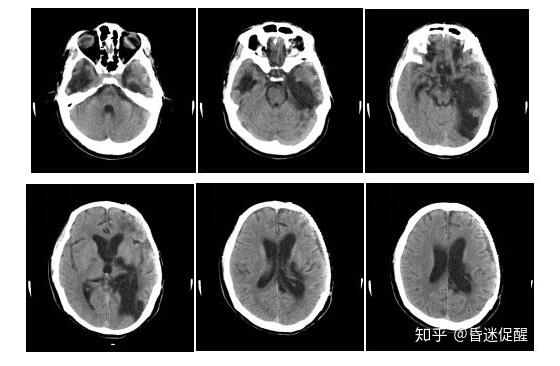

术后7个月(2018-01-05)

经过多学科团队采用综合康复技术(肢体功能障碍康复、肺功能康复、吞咽功能障碍康复、大小便失禁康复等)、神经调控技术(右正中神经电刺激)、高压氧技术、及针灸疗法等进行综合,患者终于在术后第6个月苏醒过来了,目前已能自行经口进食,正在进一步康复中。